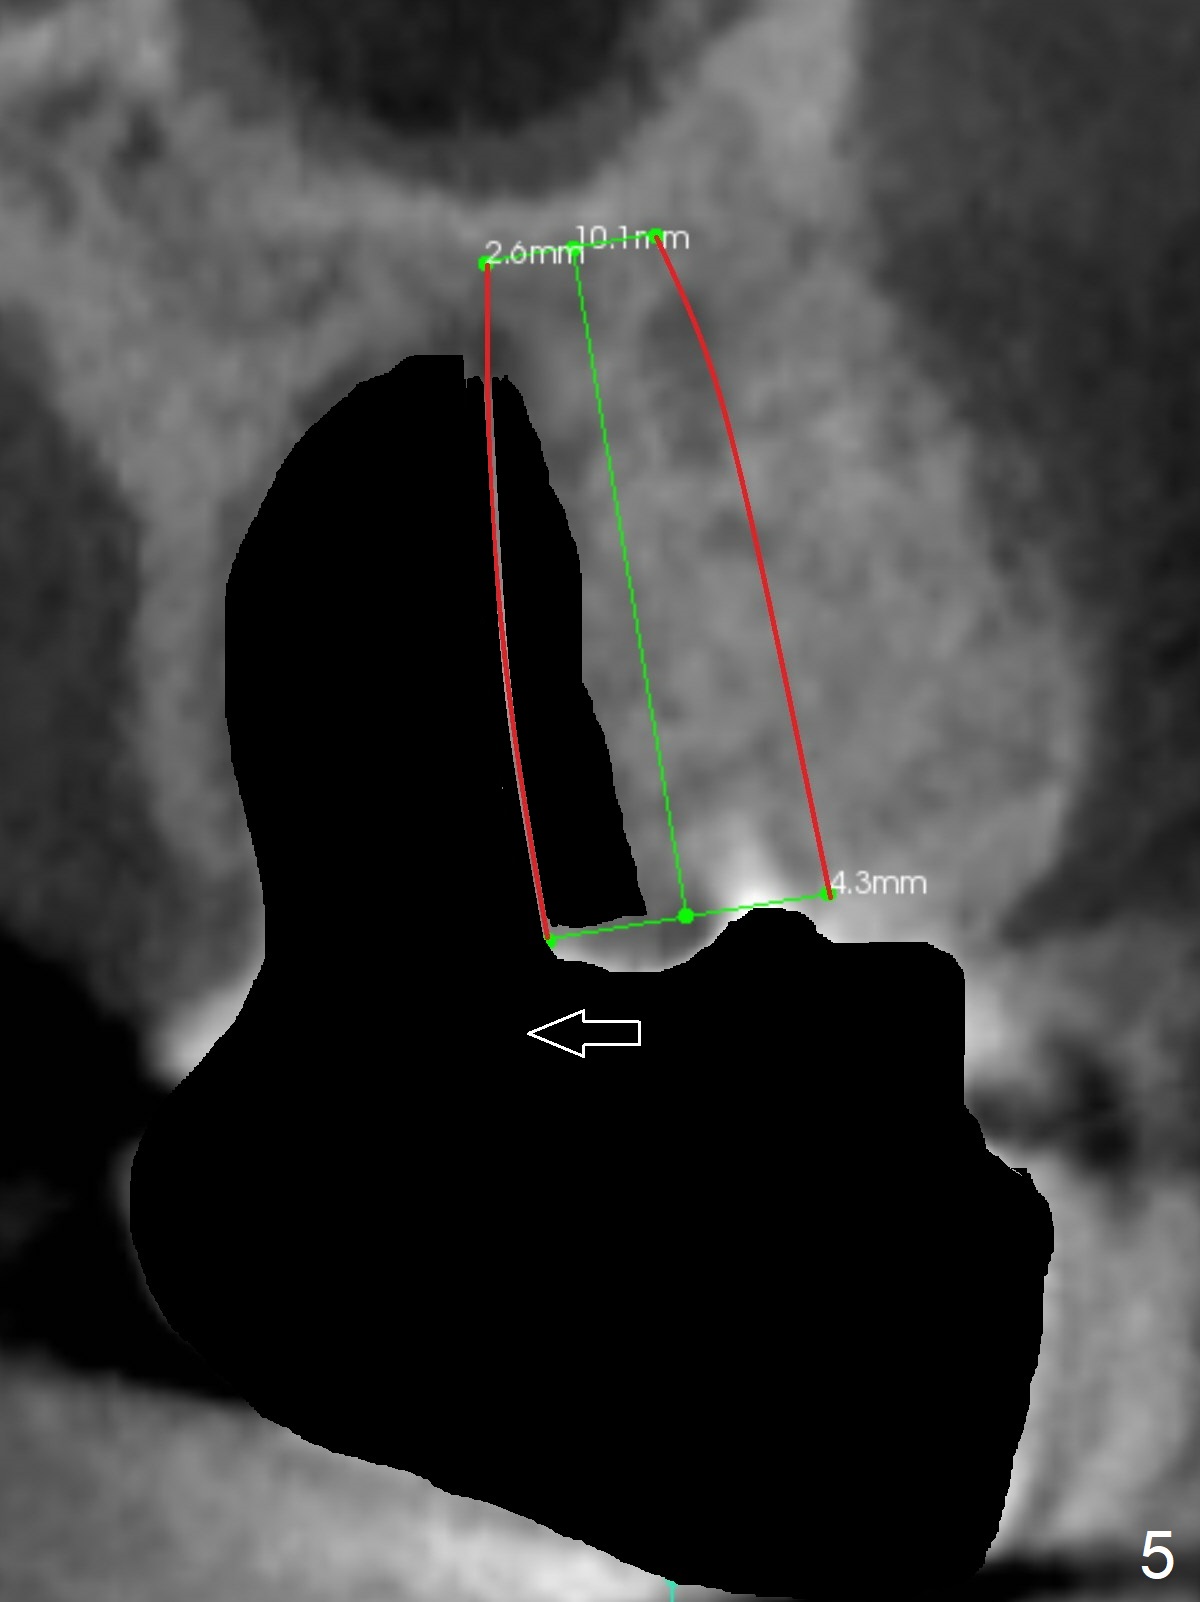

A 53-year-old man cannot chew on the left side with distal abscess in spite of RCT for #14 (* in Fig.1,2 (taken 11 ad 21 months postop, respectively)). After extraction (Fig.3 (CBCT coronal section) black area), start osteotomy with 2 mm drill (red outline) in the septum buccal to the palatal (P) socket). Following 2 mm drill removal (Fig.4), use 4.3 mm Magic Drill (red outline) for ~ 9 mm. When the osteotomy is being done, the osteotomy most likely shifts palatal (Fig.5 arrow) because of thin bone palatally. When the MD is removed (Fig.6), use Magic Sinus Lifter (Fig.7 pink) for sinus lift (arrow). The implant is to be 5x11 mm or larger. Because of the distal defect (Fig.1,2), start osteotomy mesially. Take Alginate impression before surgery for possible orthodontic treatment. Since bone density is high, use higher voltage and longer time for X-ray.